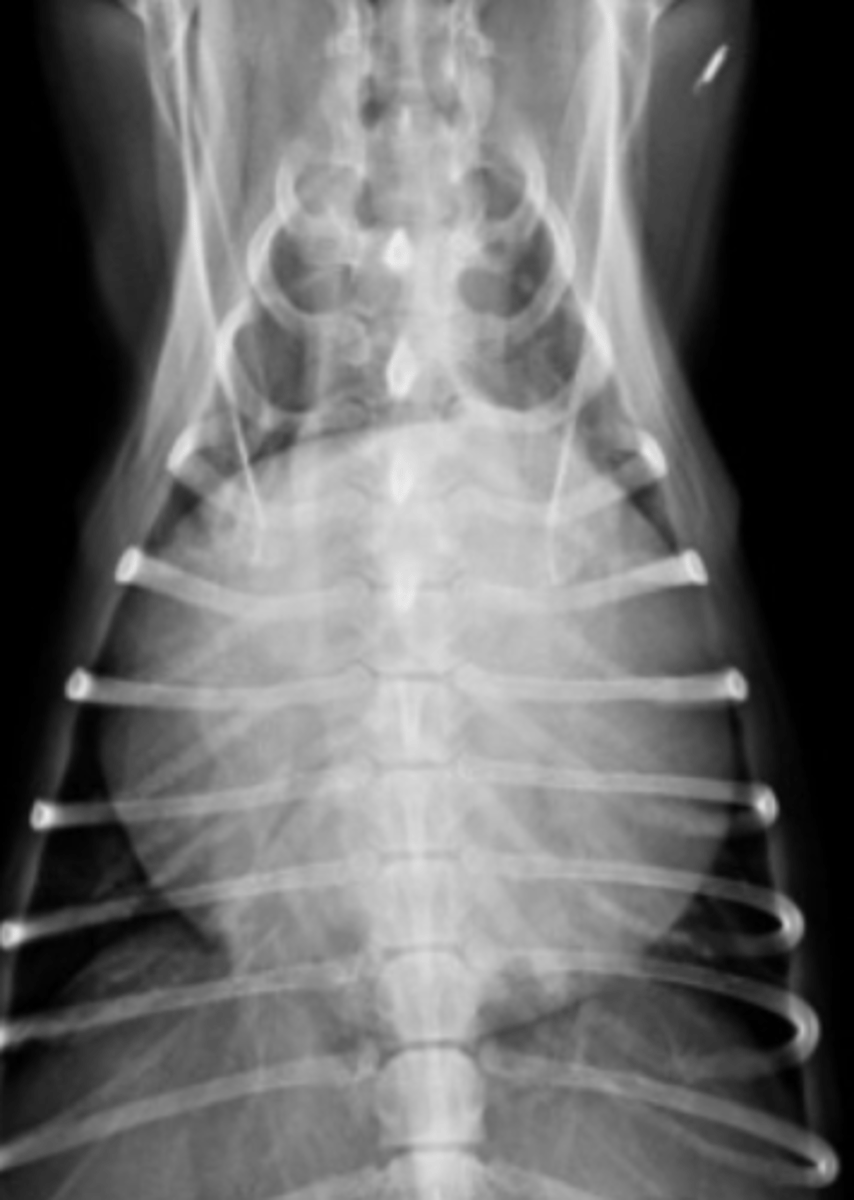

dilatación-torsión gástrica

patología: